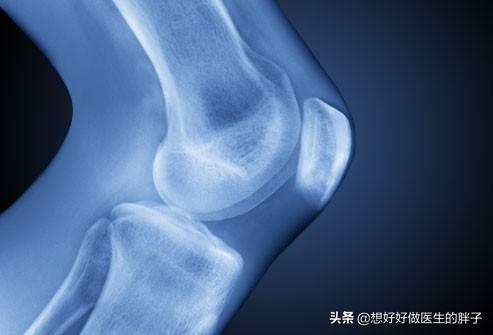

Es gibt ein klapperndes Geräusch, wenn das Kniegelenk gebeugt und gestreckt wird, ein Geräusch, das uns manchmal das Gefühl gibt, auf Schnee zu treten, ein raschelndes Geräusch.Vor allem, weil der Knorpel in den Gelenken nicht so glatt ist, wie er sein sollte.Die Begründung ist so gut wie die Begründung für die Kugellager in unseren Fahrrädern, die Körnung haben, sie ist sehr gut nachvollziehbar.

Auf der Oberfläche der Knochen des Kniegelenks, gibt es eine Schicht von Knorpel befestigt, gemeinsam in das Kniegelenk unter übermäßigem Druck Last, wird wegen der Abnutzung des Knorpels, in unserer Aktivitäten, die Schmerzen; Knorpel Verschleiß allmählich verschlimmert, wird dazu führen, dass Oberschenkelknochen und Wadenbein harte Kollision, den Verlust der Stabilität des Gelenks, und allmählich gibt es Osteomalazie, Blutzirkulation Verschlechterung, die Kühle und die knallenden Ton ist unvermeidlich.

In unseren Kniegelenken ist die Gelenkfläche mit feinem, glattem Knorpel überzogen, damit sie sich reibungslos bewegen kann. Wenn die Gelenkfläche aufgrund von Verletzungen oder Überbeanspruchung abgenutzt ist, wird sie uneben, und der Knochen gleitet bei der Bewegung des Gelenks auf der unebenen Fläche, was zu einem Klappern führt. Bei der Bewegung des Gelenks gleitet der Knochen auf der unebenen Gelenkfläche und es entsteht ein klapperndes Geräusch, das von starken Schmerzen begleitet sein kann.